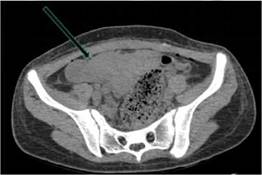

Figura 4: Tomografía de pelvis simple en proyección axial donde se observa útero en AVF de aspecto irregular incrementado de tamaño con dilatación de la cavidad endometrial y vaginal contenido hipodenso líquido, con aparente forma bicorne con cuerno rudimentario hacia anexo derecho en probable relación a obstrucción (hematómetra y hematocolpos)se evidencia además escaso liquido libre periapendicular y estriaciones de la grasa peritoneal sugestivo de proceso inflamatorio apendicular

Figura 5: Tomografía de abdomen simple corte sagital con malformación Mulleriana tipo 4. Utero didelfo de aspecto irregular aumentado de tamaño con obstrucción hipodenso de la cavidad uterina y canal vaginal.(hematómetra y hematocolpos)